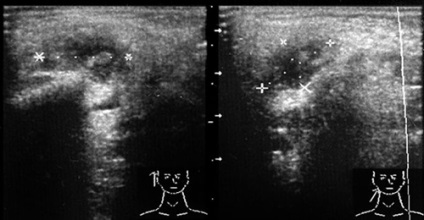

Nagy jelentősége van a finomítás a jellegét és mértékét a tumor eljárás további vizsgálatáról regionális nyirokcsomók, mint ultrahangos vizsgálat vezetője (ábra. 37).

Ábra. 37. A rosszindulatú daganatok a bal fültőmirigy (szövettanilag: adenokistoznaya karcinóma). Áttétes nyirokcsomók.

A rengeteg limfoid szövet a mirigyeket okoz nagy gyakorisággal a léziók jóindulatú vagy rosszindulatú limfoproliferatív rendellenességek, amelyek szintén megvan a saját jellemző echográfiás jelek (ábra. 38-39).

Ábra. 38. A vereség maradt fültőmirigy limfoproliferatív betegség (szövettanilag: limfóma).

Ábra. 39. nyirokcsomók a nyakon limfoproliferatív betegség (szövettanilag: lymphosarcoma).